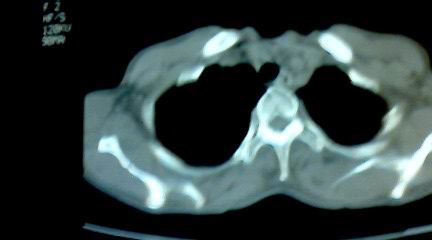

标题: CT25218:请教!胸部CT,胸8椎体骨质破坏,伴周围软组织肿。 [打印本页]

标题: CT25218:请教!胸部CT,胸8椎体骨质破坏,伴周围软组织肿。

患者,女41岁,肢体乏力。

两肺上叶继发性肺结核;胸椎结核并椎旁寒性脓肿形成。

胸椎结核并椎旁寒性脓肿形成。